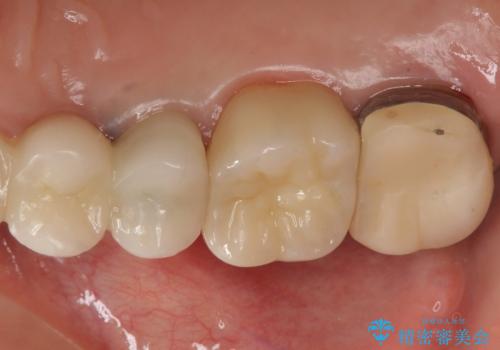

向かい合わせの歯の咬みこみが強くインレーよりも強度の高いクラウンでの治療となりました。その中でも色が白くある程度の薄さでも耐久性を発揮するフルジルコニアクラウンでの修復を行いました。適合も良く色調もとてもなじんだため大変喜んでいただけました。